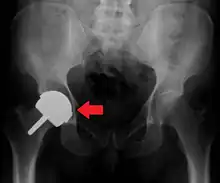

Osteolysis

Many long-term problems with hip replacements are the result of osteolysis. This is the loss of bone caused by the body's reaction to polyethylene wear debris, fine bits of plastic that wear off the cup liner over time. An inflammatory process causes bone resorption that may lead to subsequent loosening of the hip implants and even fractures in the bone around the implants. Ceramic bearing surfaces may eliminate the generation of wear particles. Metal cup liners joined with metal heads (metal-on-metal hip arthroplasty) were developed for similar reasons. In the lab these show excellent wear characteristics and benefit from a different mode of lubrication.

Highly cross-linked polyethylene plastic liners experience significantly reduced plastic wear debris. The newer ceramic and metal prostheses may not have long-term performance records. Ceramic piece breakage can lead to catastrophic failure. This occurs in about 2% of implants. They may also cause an audible, high pitched squeaking noise with activity. Metal-on-metal arthroplasty can release metal debris into the body. Highly cross linked polyethylene is not as strong as regular polyethylene. These plastic liners can crack or break free of the metal shell that holds them.